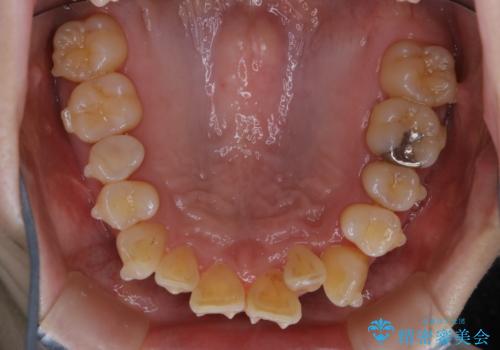

- インビザラインでのマウスピース矯正中に、歯の黄ばみが気になるため綺麗に白くしたいとのことでした。PMTC60分コースを行いました。

PMTC(保険外治療)は、毎日の歯磨きで落としきれない汚れや、コーヒ、紅茶・タバコのヤニなどの着色も除去します。目には見えない歯と歯の間・歯肉の境目・インビザライン中はアタッチメント周囲などに残っているプラーク(歯垢)もしっかり取り除きます。PMTCでは専門的な機械や材料を使用して、徹底的に汚れを除去するため、虫歯・歯周病・口臭予防などにつながります。

またPMTCを行うことで、ご自身本来の歯の色になり自然な明るさになります。